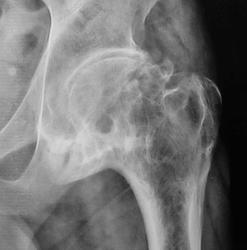

Исход Легг-кальве- пертеса в виде деф. артроза 3.

Жалуется на боли в тазобедренном суставе.

Пациент ранее был обследован МРТ, со слов пациента - виллезонодулярный синовит. Конечно понятно, что тут, не один синовит. Обследование было в платной клинике (три кабинетика приема) и на очень дорогом МРТ.